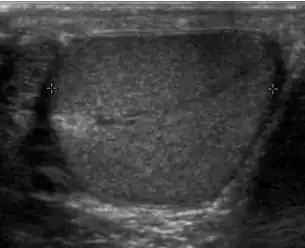

At ultrasound, tuberculous epididymitis is characterized by an enlarged epididymis with variable echogenicity. The presence of calcification, caseation necrosis, granulomas and fibrosis can result in heterogeneous echogenicity [Fig. 21a]. The ultrasound findings of tuberculous orchitis are as follow: (a) diffusely enlarged heterogeneously hypoechoic testis (b) diffusely enlarged homogeneously hypoechoic testis (c) nodular enlarged heterogeneously hypoechoic testis and (d) presence of multiple small hypoechoic nodules in an enlarged testis [Fig. 21b].